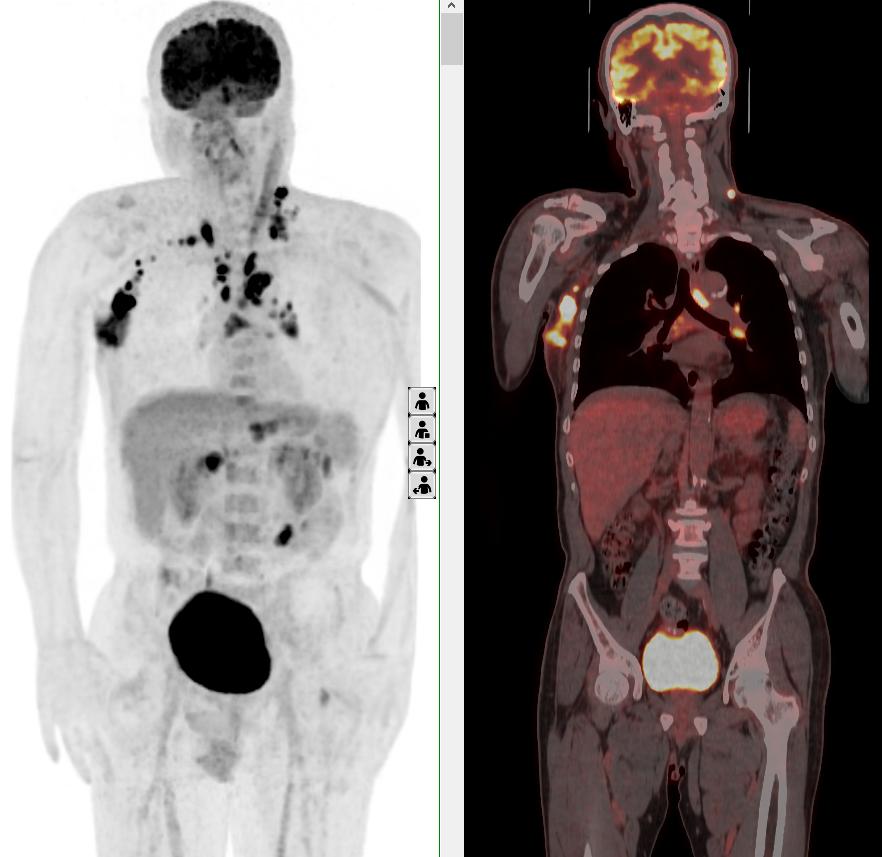

完善PET/CT檢查示:右側(cè)腋窩、雙側(cè)中下頸部、縱隔、雙側(cè)肺門多發(fā)MT,建議淋巴結(jié)活檢。后患者行右腋窩淋巴結(jié)切除活檢術(shù),經(jīng)北京大學(xué)第三醫(yī)院病理科會診示:右腋窩淋巴結(jié)惡性腫瘤,呈淋巴竇內(nèi)生長模式,瘤細(xì)胞呈上皮樣,異型性明顯,伴中性粒細(xì)胞浸潤。結(jié)合病史及免疫組化,考慮為SMARCA4(BRG1)缺失的胸部腫瘤,伴神經(jīng)內(nèi)分泌標(biāo)記表達(dá)。

本例為罕見病理類型的腫瘤,影像學(xué)表現(xiàn)無明顯特異性,診斷困難。強(qiáng)化CT和穿刺病理已基本明確為惡性腫瘤,行PET/CT檢查一是為了全身檢查,完善分期,二是根據(jù)PET代謝情況指導(dǎo)進(jìn)行生物靶區(qū)活檢,進(jìn)一步明確病理診斷。最終,PET/CT除縱隔病變外發(fā)現(xiàn)更多頸胸部淋巴結(jié)代謝異常,綜合考慮后對腋窩淋巴結(jié)進(jìn)行切除活檢,最終得到病理證實(shí)。